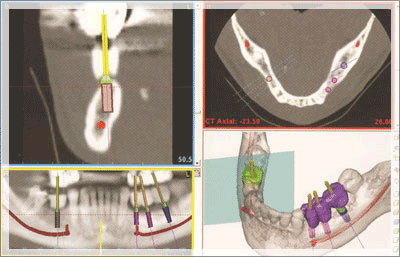

治療計画

ガリレオスとセレックから得らえれたデータを元にシミュレーションソフトでインプラントのプランニングを行います。実際の手術をアクティブに再現します。審美・機能回復を入念にシミュレートしていきます。

インプラント埋入を正確に行うために必要なサージカルガイドをセレックにより作成します。全てデジタルデータによる移行と院内での作成が可能なため、正確性はもちろん、時間やコストを削減することができます。